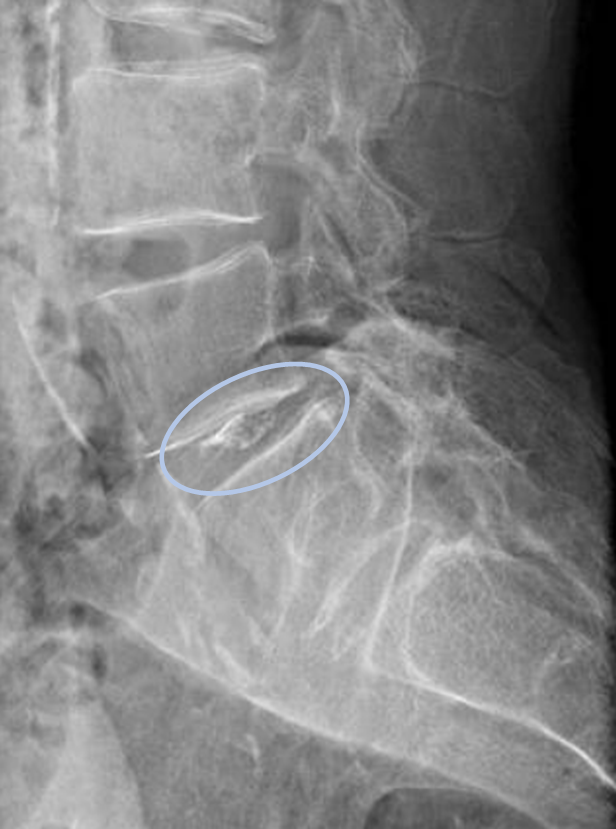

画像及び所見について

• L5/s-椎間板変性

以上の事が画像上認められます。

・L5/s-椎間板変性による右椎間孔狭窄を認め、主症状の原因の可能性がある